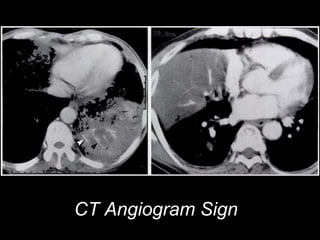

CT Angiogram Sign